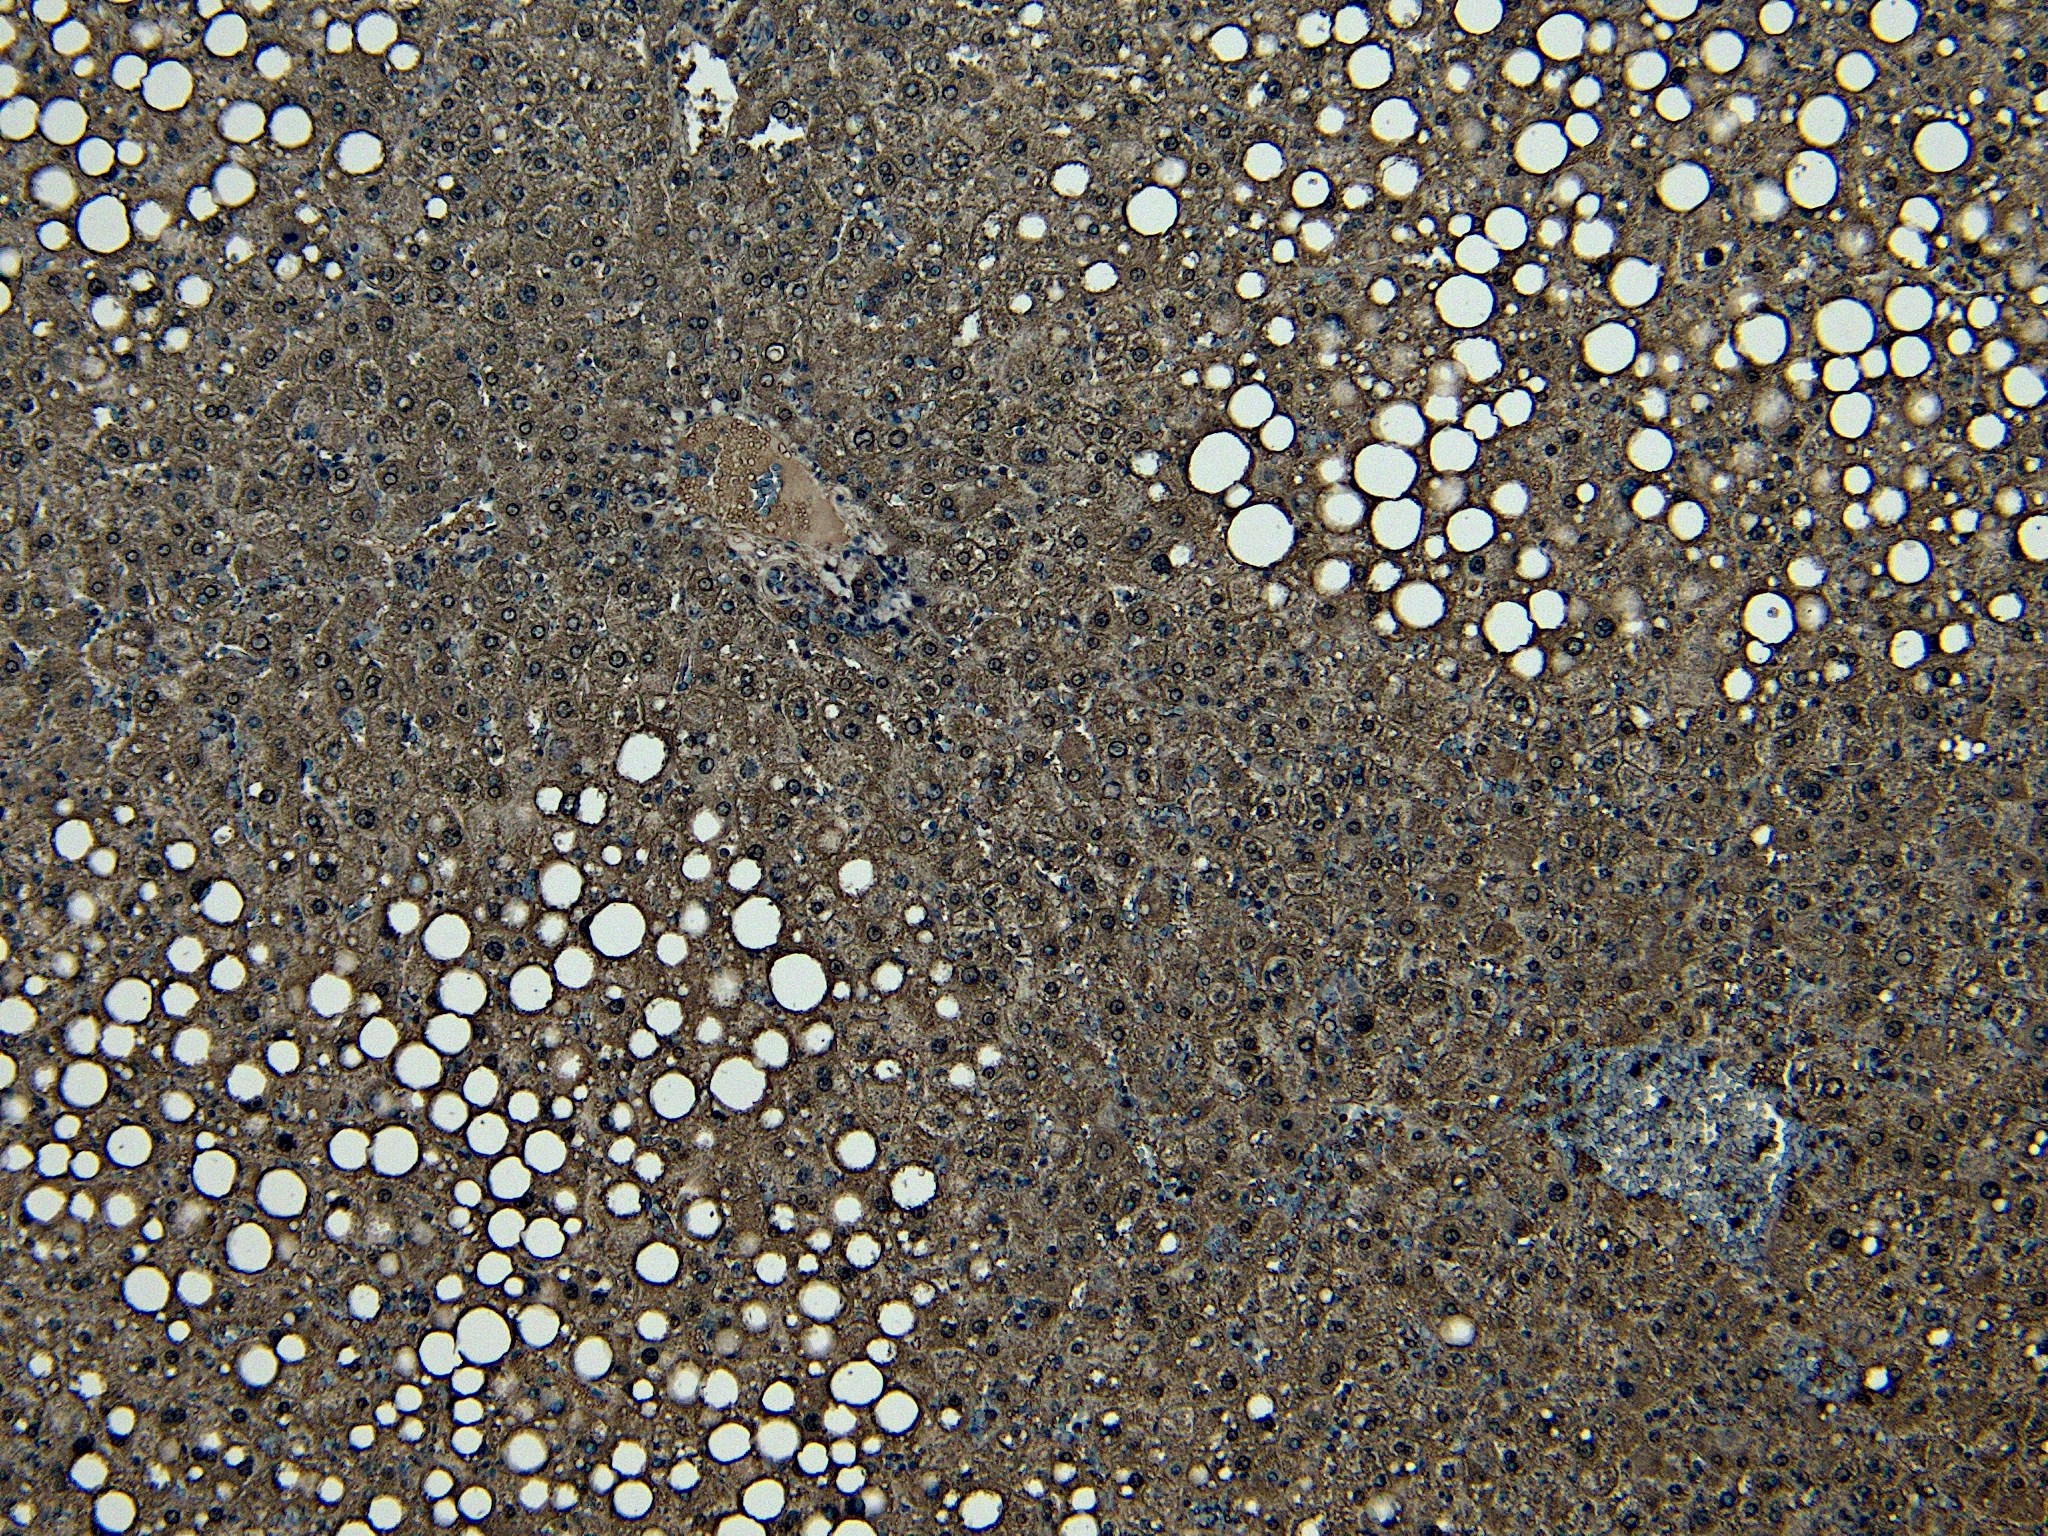

IHC Results Paraffin embedded Human Liver. Recommended concentration: 5-7µg/ml. | |